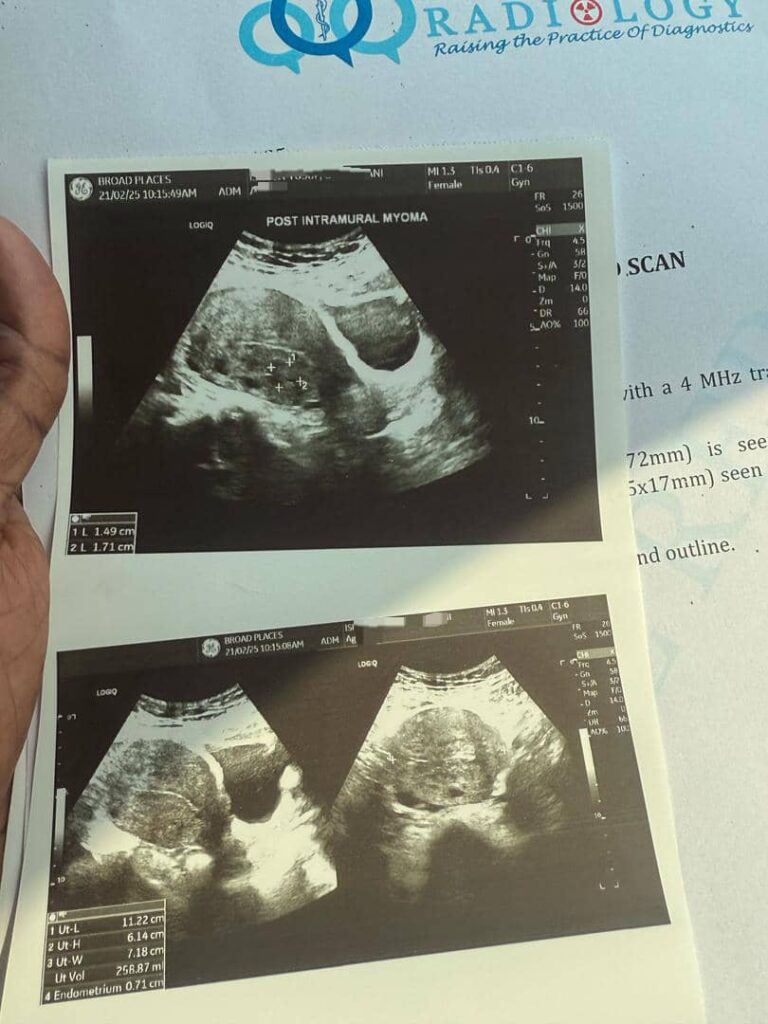

Madam blessing’s case of 3 intramural myomata in the anterior(47x33mm), posterior(41x23mm) and fundal(34x33mm) uterine body shrunk drastically to just(15x17mm) within a month of using ultimate fibroid crusher

with permission from some of our patients, see the shocking scan results of how fibroid reduced over time while using ultimate fibroid crusher.